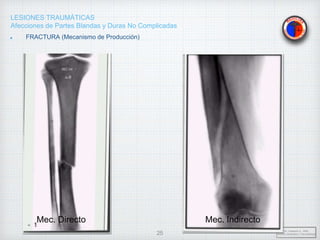

FRACTURA (Mecanismo de Producción)

• Mecanismo Directo: El agente causal

actúa directamente sobre el foco de

fractura(Área circunscrita al trazo de

Fractura).

• Mecanismo Indirecto: El agente

traumático actúa a cierta distancia del

foco de fractura.

Mec. Directo Mec. Indirecto